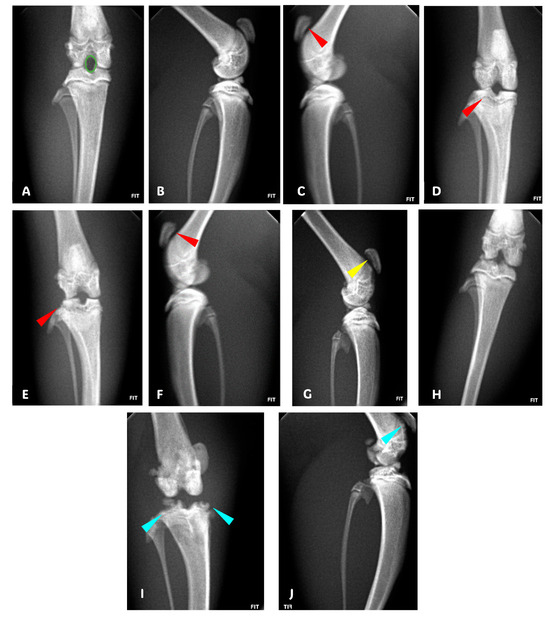

Radiological evaluations indicated that the sham group maintained nearly perfect joint integrity, scoring between 0 and 1, reflecting intact articulating surfaces and bone structure (Figure 2A,B and Figure 1D). The separate cuminaldehyde- and indomethacin-treated groups showed mild to moderate articular changes, scoring 2.1 and 1.6, respectively, with damage primarily in the lateral and patellofemoral compartments (Figure 2C–F and Figure 1D). The combined treatment of cuminaldehyde and indomethacin resulted in mild lesions mainly in the patellofemoral compartment, scoring 1.4 (Figure 2G,H and Figure 1D). The saline-treated group exhibited severe OA features, scoring 3.4, including complete cartilage erosion, bone loss, and, in severe cases, joint subluxation (Figure 2I,J and Figure 1D).

Figure 2. Anteroposterior (AP) and lateral radiographs demonstrating congruence between the tibial and femoral condyles and the intercondylar space in the lateral view showing intact space between the patella and femur (A,B; Sham Group); bicompartimental patellofemoral and lateral lesion [red arrowhead] (C,D; Cuminaldehyde Group); bicompartimental patellofemoral and lateral lesion [red arrowhead] (E,F; Indomethacin Group); unicompartimental patellofemoral component only lesion [yellow arrowhead] (G,H; cuminaldehyde + indomethacin Group); and dystrophy, osteopenia, and bone loss with incongruence between the sizes of the condyles and intercondylar space associated with reduction in the joint space; in the lateral view, we observe destruction of the articular cartilage, bone loss of the patella, and complete destruction of the knee joint induced with MIA with calcifications and joint subluxation [cyan arrowhead] (I,J; Saline Group).